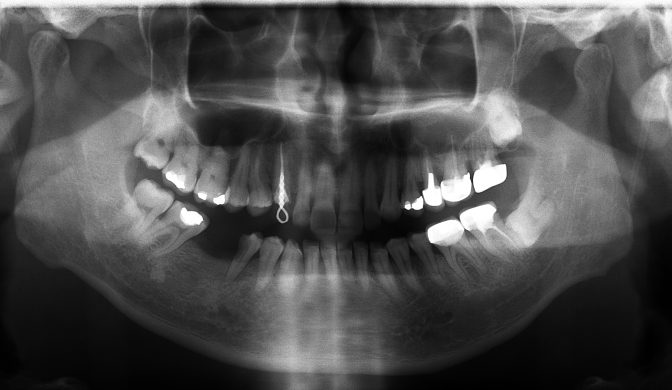

01

SST

| implant model | SST |

|---|---|

| surgery date | 2010.06.09 |

| gender | Female |

| age | 30 |